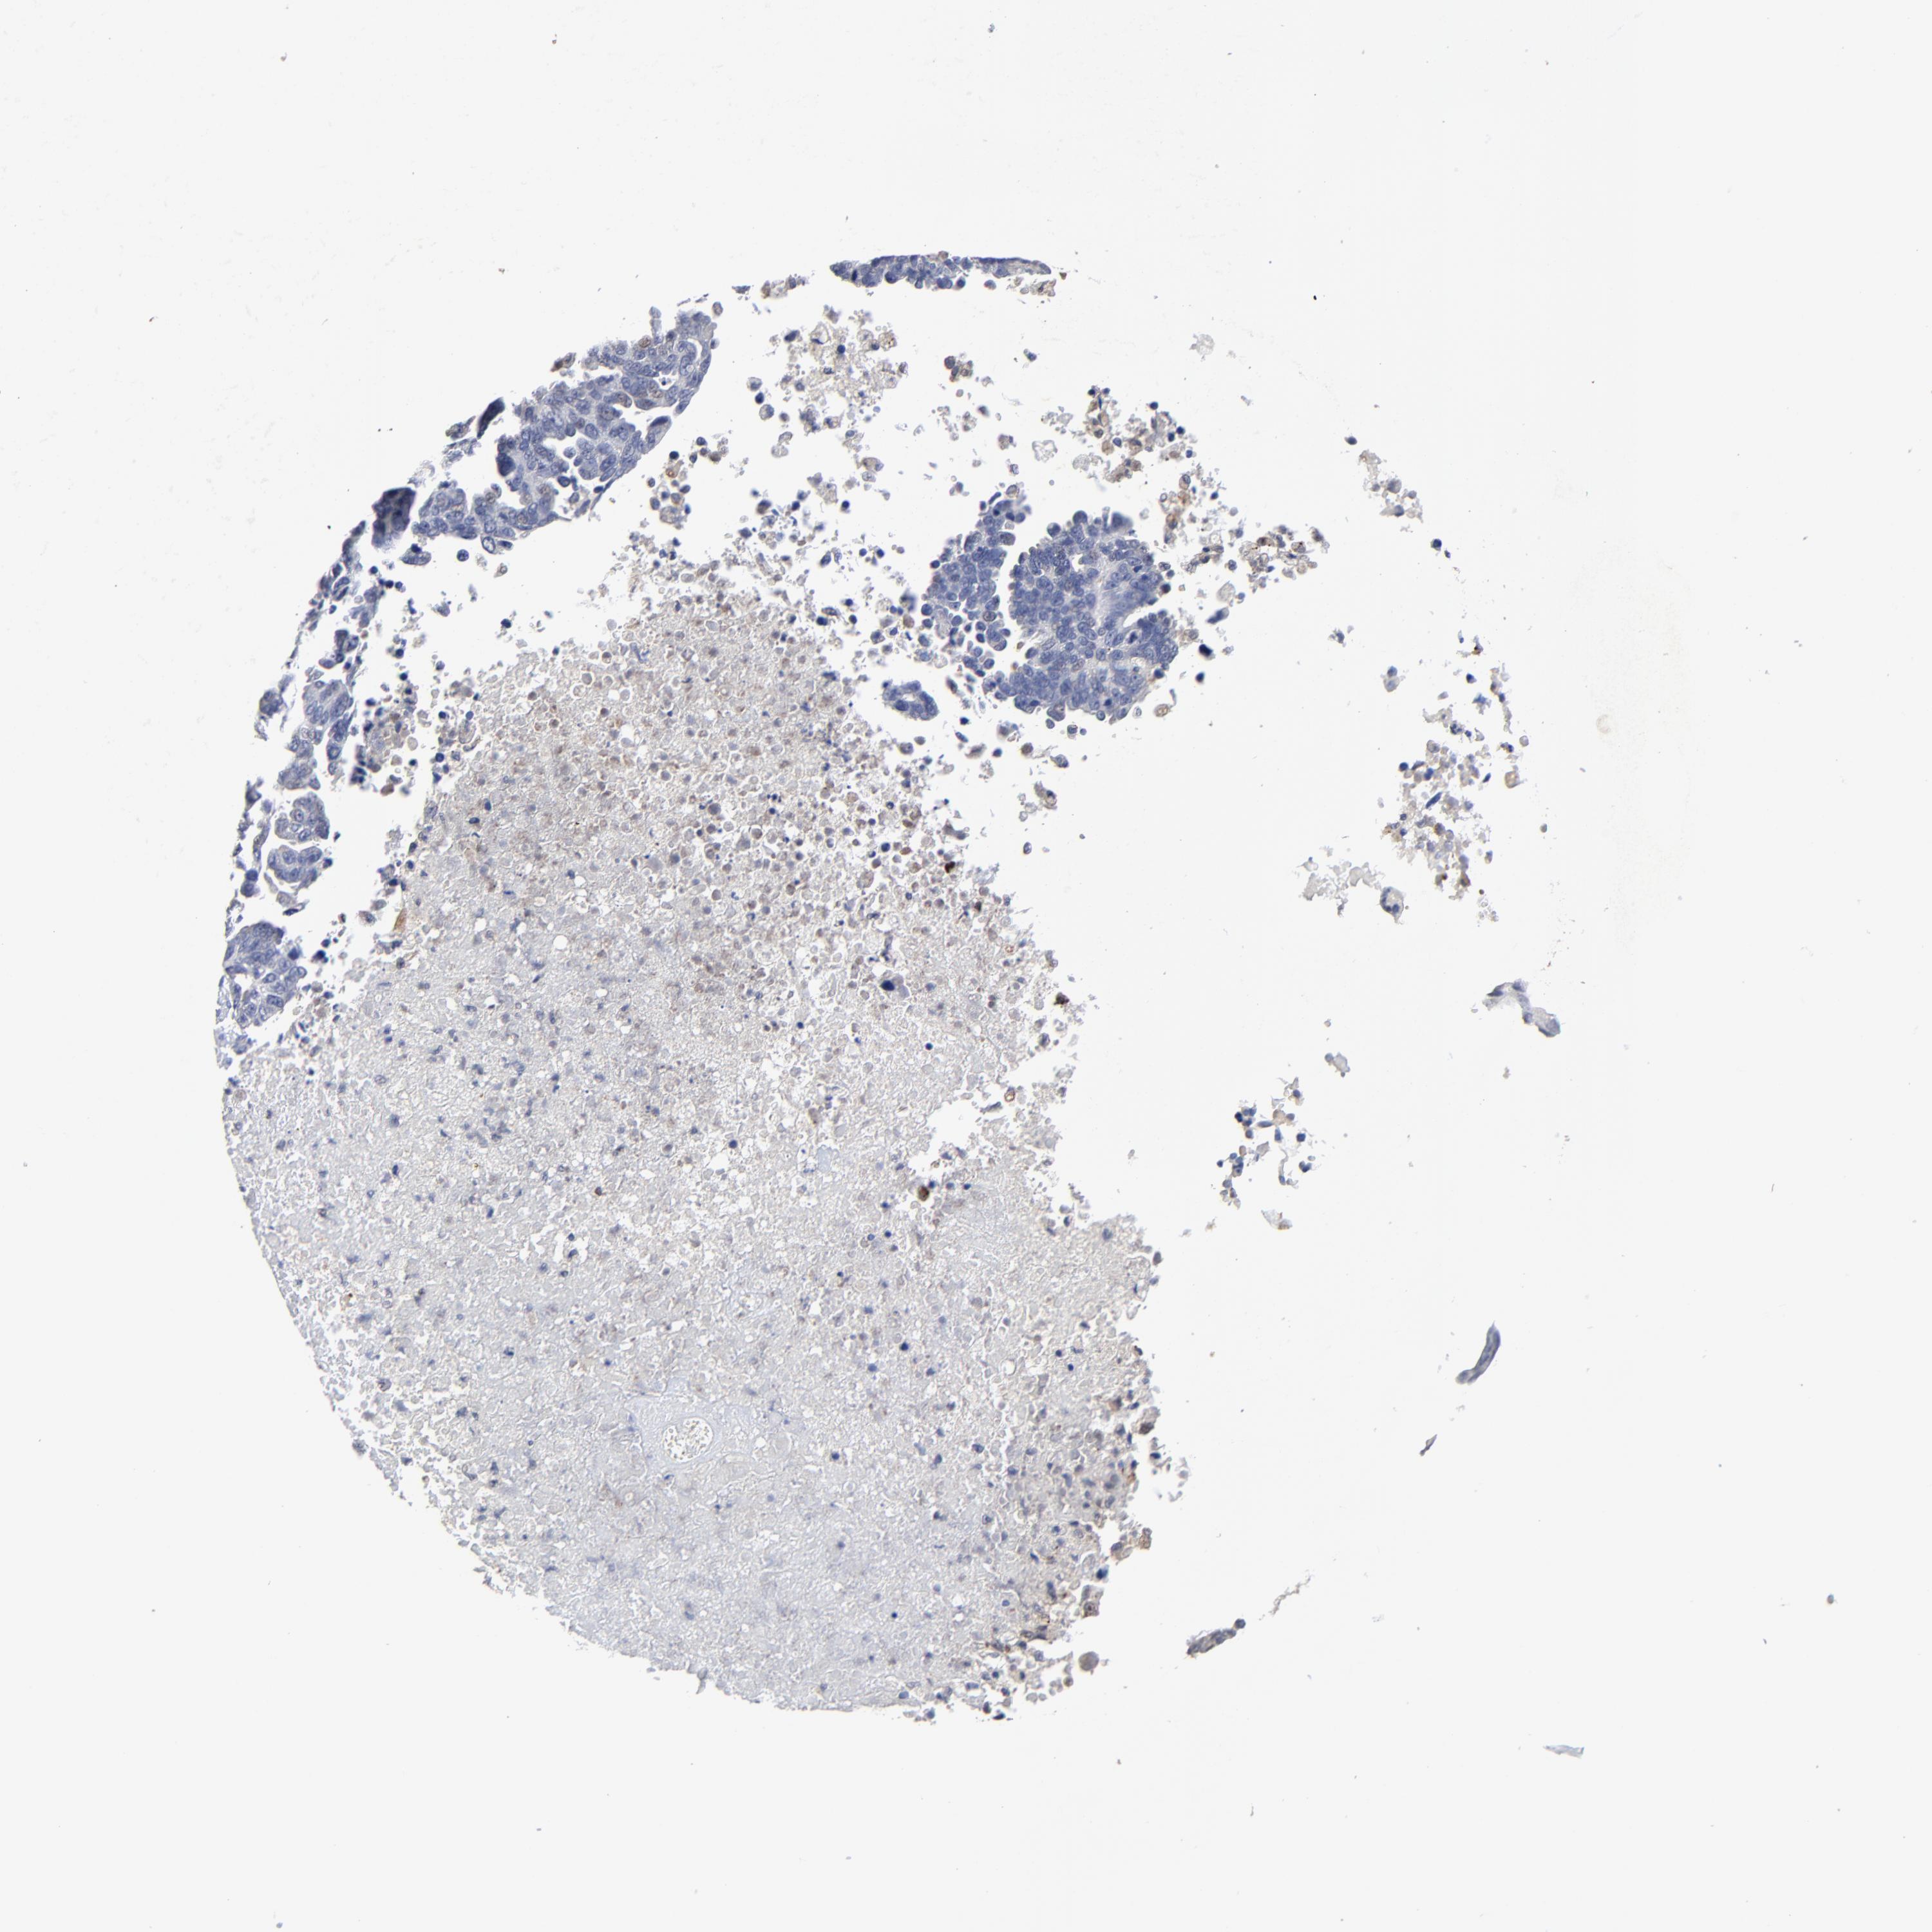

OVARIAN CANCER - Protein expressioni

A mouse-over function shows sample information and annotation data. Click on an image to view it in a full screen mode. Samples can be filtered based on level of antibody staining by selecting one or several of the following categories: high, medium, low and not detected. The assay and annotation is described here.

Note that samples used for immunohistochemistry by the Human Protein Atlas do not correspond to samples in the TCGA dataset.

Antibody stainingi

Antibody staining in the annotated cell types in the current human tissue is reported as not detected, low, medium, or high, based on conventional immunohistochemistry profiling in selected tissues. This score is based on the combination of the staining intensity and fraction of stained cells.

Each image is clickable and will lead to virtual microscopy that enables deeper exploration of all samples and also displays staining intensity scores, fraction scores and subcellular localization as well as patient and tissue information for each sample.

Antibody HPA003162

Antibody CAB005191

Staining

High

Medium

Low

Not detected

Intensity

Strong

Moderate

Weak

Negative

Quantity

>75%

75%-25%

<25%

None

Location

Nuclear

Cytoplasmic/membranous

Cytoplasmic/membranous,nuclear

Cystadenocarcinoma, mucinous, NOS

Carcinoma, endometroid

Cystadenocarcinoma, serous, NOS

Carcinoma, NOS